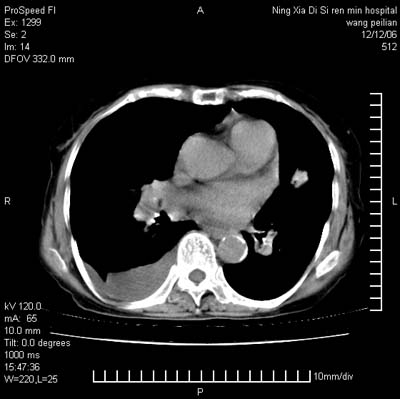

标题: CT5609:胸部:女77 病史不详 [打印本页]

标题: CT5609:胸部:女77 病史不详

两肺可见多个大小不等的结节,左侧有胸水,纵隔淋巴结增大,考虑是细支气管肺泡癌

两肺尖纤维索状影,两下肺结节块状影,且有钙化灶,右胸腔积液。考虑肺结核并胸膜炎。

两肺尖纤维索状影,两下肺结节块状影,且有钙化灶,右胸腔积液。考虑肺结核并胸膜炎肺间质纤维化

考虑:1、慢性支气管炎合并全小叶型肺气肿、间质纤维化;

2、双肺结核;

3、右侧胸膜炎(积液)。

1、双肺继发型肺结核(以纤维、增殖灶为主);

2、右侧胸腔积液;

3、其余符合老年肺改变。

双肺见多个结节状及条索状影,双侧胸腔积液,右侧叶间积液,考虑结核性胸膜炎